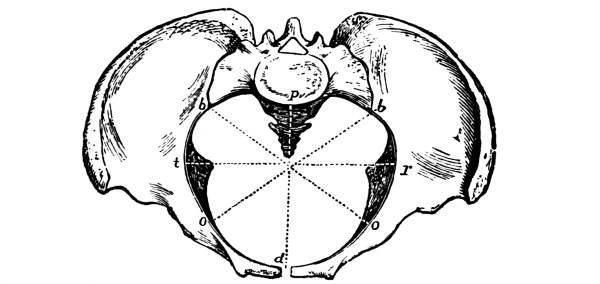

| The Pelvis and the Genital Organs | 161 |

The Pelvis, 161—The Male Generative Organs, 164—The Prostate Gland, 164—The Testes, 165—The Penis, 165—The Female Generative Organs, 165—The Ovaries, 165—The Fallopian Tubes, 166—The Uterus, 167—The Vagina, 168—The External Genitalia in the Female, 169—The Vulva, 169—The Mons Veneris, 169—The Labia Majora, 169—The Labia Minora, 170—The Clitoris, 170—The Meatus Urinarius, 170—The Hymen, 170—The Fourchette, 170—The Perineal Body, 170—The Perineum, 170. |